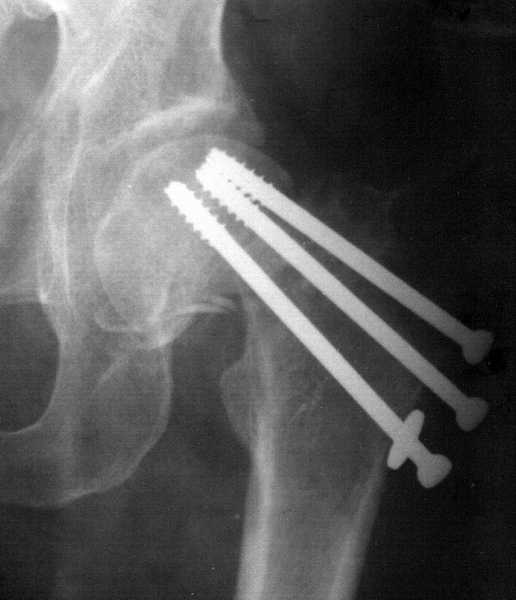

Неудача после остеосинтеза шейки бедра

У мужчины 49 лет, перенесшего 10 лет назад инсульт с гемипарезом, 6 февраля этого года был выполнен остеосинтез шейки бедра канюлированными винтами через 2 недели после перелома (на стороне пареза).

До травмы он ходил без дополнительной опоры, хотя функция после инсульта восстановилась не полностью. На недавних снимках выявилась несостоятельность фиксации. Встает вопрос - что предпринять?Мне кажется, выбор тут между эндопротезированием и вальгизирующей остетомией. Хотя коллеги из другого учреждения высказывались за артродез ввиду опасности вывихов эндопротеза. Спасибо за Ваше мнение.